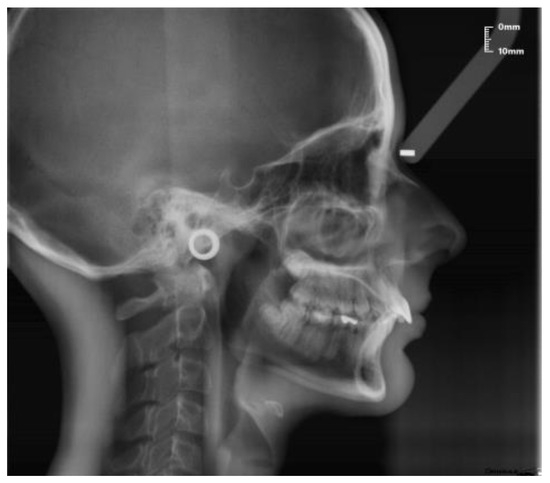

- Sagittal plane:

- Angle formed by the long axis of the incisor and the palatine plane—CP angle.

- Angle formed by the long axis of the incisive canal and the palatine plane—IP angle.